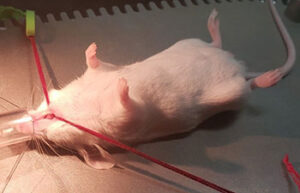

- Surgery and biopsy

- Animal injections: subcutaneous, intramuscular, intravenous and peritoneal